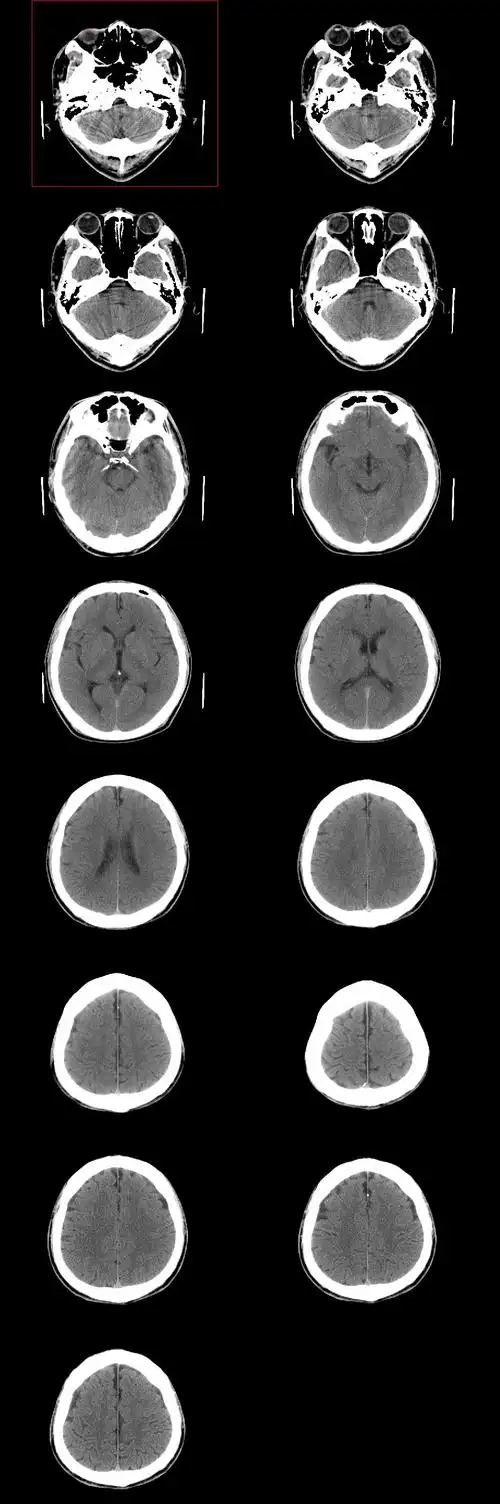

头颅ct平扫显示脑皮层萎缩.